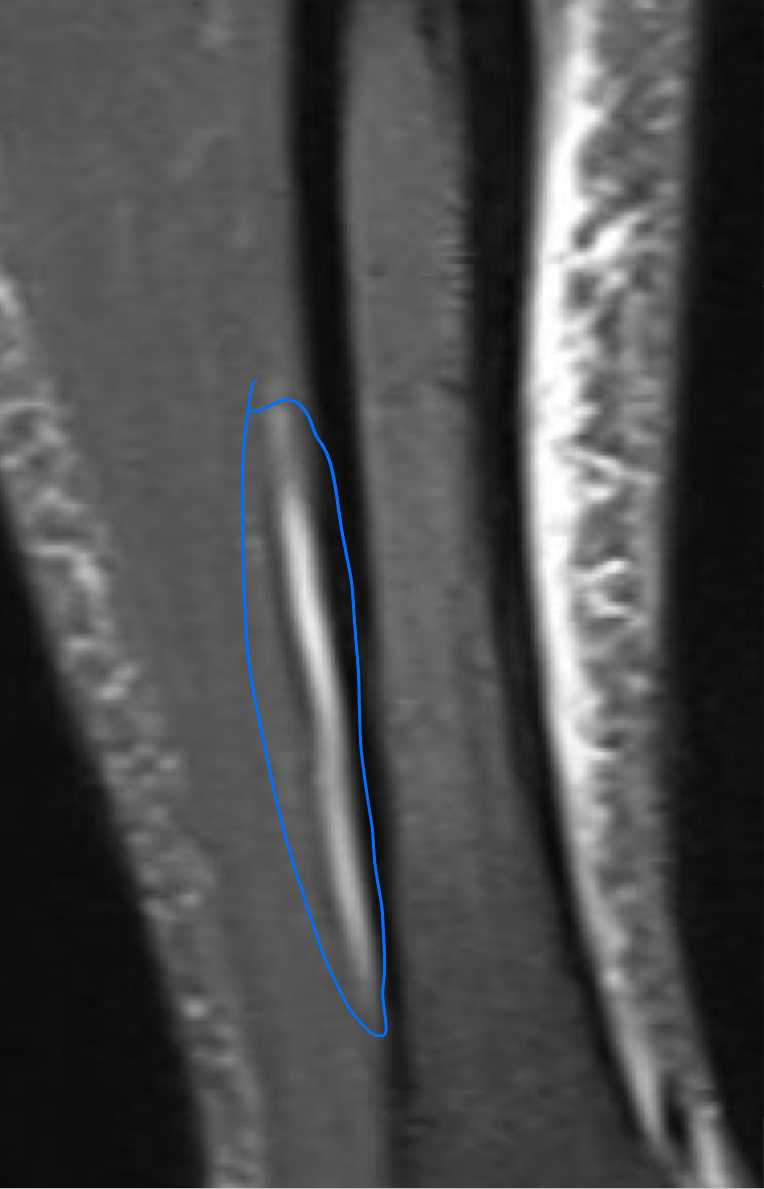

STIR MRI

Coronal STIR (fat signal suppressed) MRI of a lower leg showing high signal (bright) areas around the tibia as signs of stress fracture